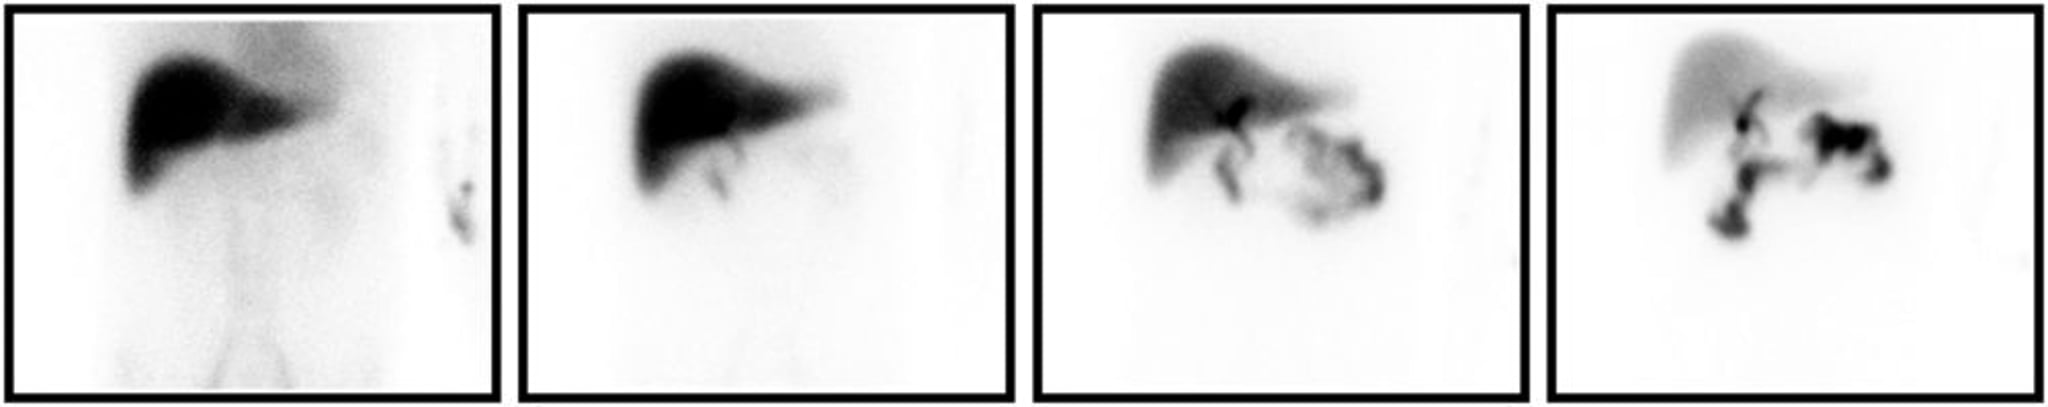

ГИДК-сканирование

Данные ГИДК-сканирования указывают на холецистит. Слева направо представлены изображения, полученные через 5, 15, 30 и 60 минут после введения радиофармпрепарата. Даже в конечные контрольные моменты времени желчный пузырь остается незаполненным.